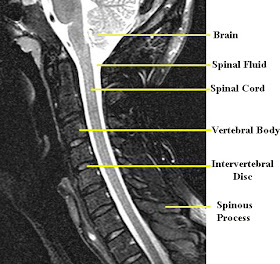

First, here is a picture of a normal Cervical Spine MRI. You can see how the spinal cord maintains it's shape up the entire spinal column, and there is a pretty equal amount of spinal fluid around it all the way up the length as well.